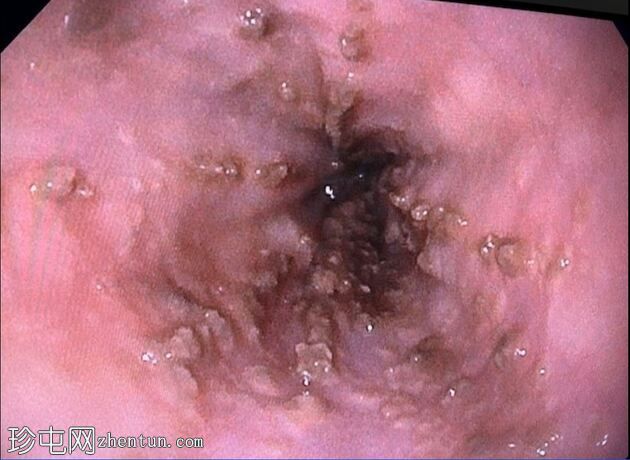

照片

十二指肠壁溃疡

内镜报告:

食管:LA C级食管炎。

胃:胃底可见变质血液及大血块。吸痰、冲洗并调整患者体位以移动血块后,未在胃底或胃体部发现病变。未发现活动性出血点。

胃窦:幽门前区可见三处溃疡,每处均小于1厘米,底部均清洁。

十二指肠:

D1:D1前壁可见一处含血块的溃疡。应用两个止血夹止血,并在溃疡周围注射1:10,000肾上腺素。

D2:D2可见两处溃疡。